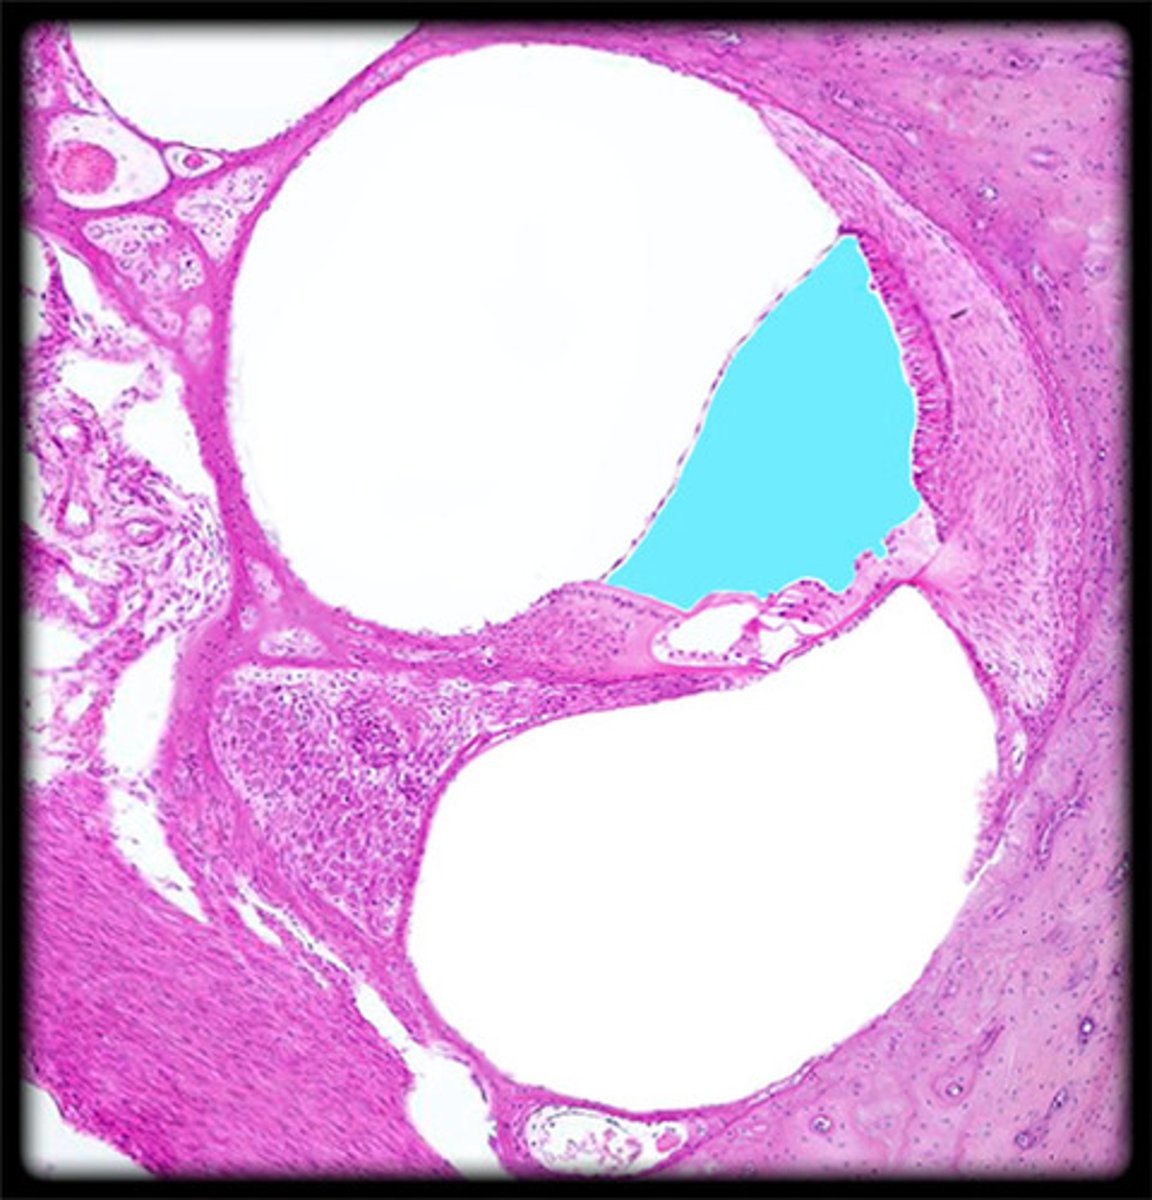

cochlea histology

scala vestibuli

contains perilymph

scala media

contains endolymph

scala tympani

vestibular membrane

organ of Corti

tissue containing the hair cells necessary for hearing

basilar membrane